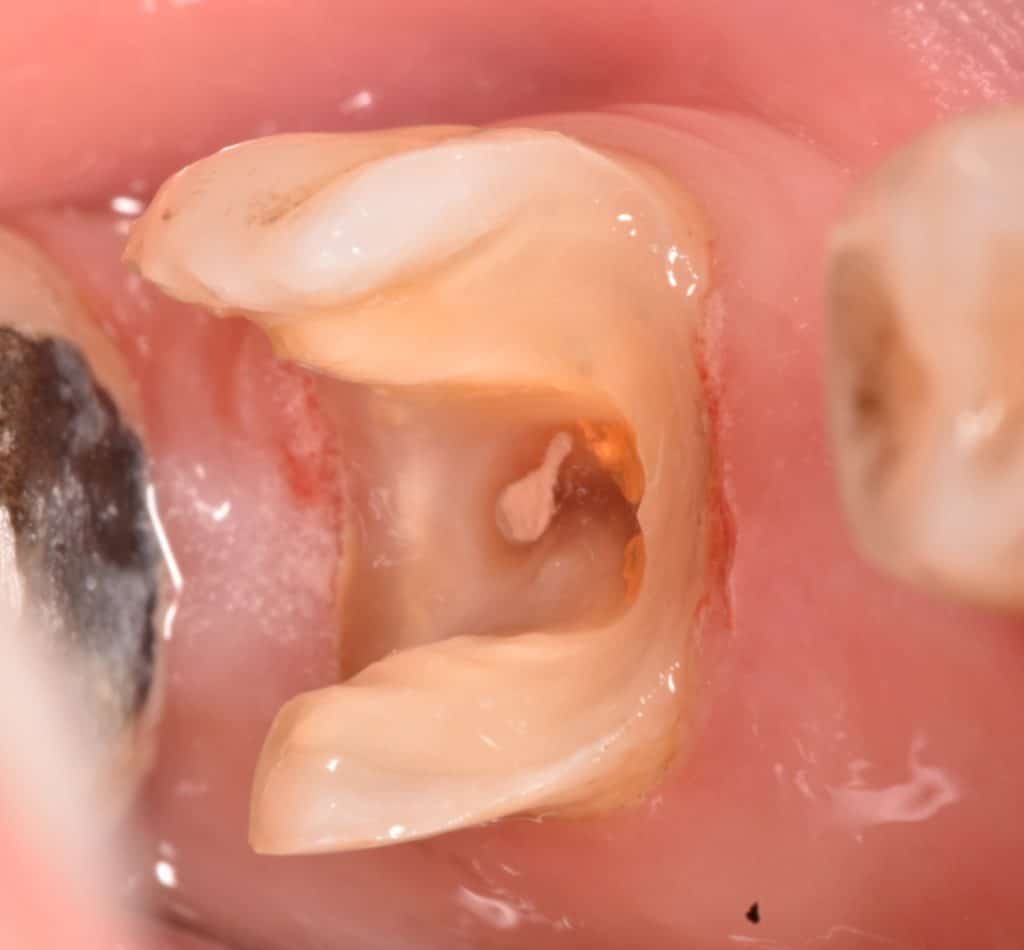

Tooth preparation for cementation ,first isolation ,second sandblasting, third acid etching, fourth adhesive without curing

Overlay preparation for cementation , first : HF 9.6% acid etching for 20 sec. , second : phosphoric acid etching for 1min. ,third : silane application for 1min. And dry , bond without curing (some literature said its not necessary ) , cementation with heated composite